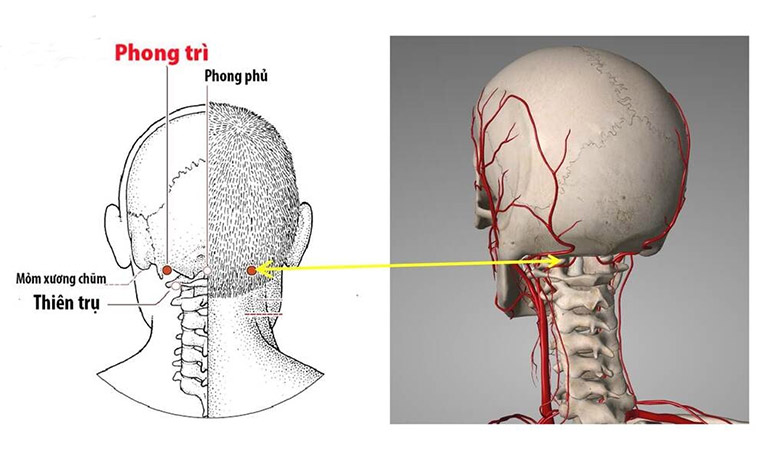

1. Huyệt Phong Trì: Phù hợp với người căng thẳng, tăng huyết áp, thường xuyên đau đầu vùng gáy kèm hoa mắt.

– Vị trí: Đặt hai ngón tay cái vào phía sau gáy, ngay dưới xương sọ; dịch nhẹ ra hai bên cho đến khi ngón tay rơi vào hai hõm nhỏ, nằm giữa hai bó cơ cứng, đó là vị trí của huyệt Phong Trì.

– Tác dụng: Giúp thư giãn cơ vùng cổ gáy, tăng lưu thông máu lên vùng đầu, từ đó hỗ trợ giảm chóng mặt và cảm giác ù tai.

– Cách thực hiện: Dùng hai ngón tay cái day ấn đồng thời hai bên trong khoảng 1–2 phút, lực vừa phải, cảm giác căng tức nhẹ là phù hợp.

Day bấm huyệt Phong Trì giúp thư giãn cơ vùng cổ gáy, tăng lưu thông máu lên vùng đầu, giảm chóng mặt.